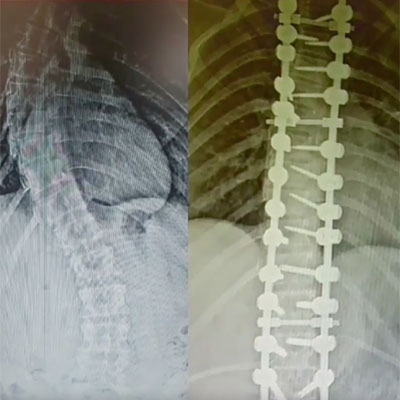

İşlem Görüntüleri

Skolyoz, omurganın yandan bakıldığında S veya C şeklinde eğrilik gösterdiği bir omurga hastalığıdır. Genellikle çocukluk ve ergenlik döneminde başlayan bu durum, omurganın düzgün hizalanmasını engeller. Skolyozun nedeni tam olarak bilinmese de, çevresel, genetik veya nöromüsküler faktörlerle ilişkili olabileceği düşünülmektedir. Hafif vakalardan ciddiye kadar değişen şiddette görülebilir ve bazı durumlarda belirti vermeden ilerleyebilir. Ancak ilerleyen vakalarda, omurga eğriliği ve eşlik eden postür bozukluğu nedeniyle fiziksel rahatsızlıklara, sırt ve bel ağrısına, solunum güçlüklerine ve organlara baskıya neden olabilir. Erken teşhis ve tedavi, skolyozun ilerlemesini engellemeye ve yaşam kalitesini artırmaya yardımcı olabilir.

Omurganın ön ve arkadan bakıldığında 8 - 10 derece üzerindeki sağ veya sol tarafa olan eğriliği ile buna eşlik eden, kendi ekseni etrafındaki dönme hareketinin (rotasyon ) oluşturduğu bir şekil bozukluğudur. Skolyoz omurga deformiteleri içerisinde en sık karşılaştığımız ve ilerleyen evrelerde ciddi duruş bozukluklarına neden olan üç boyutlu bir omurga deformitesidir.